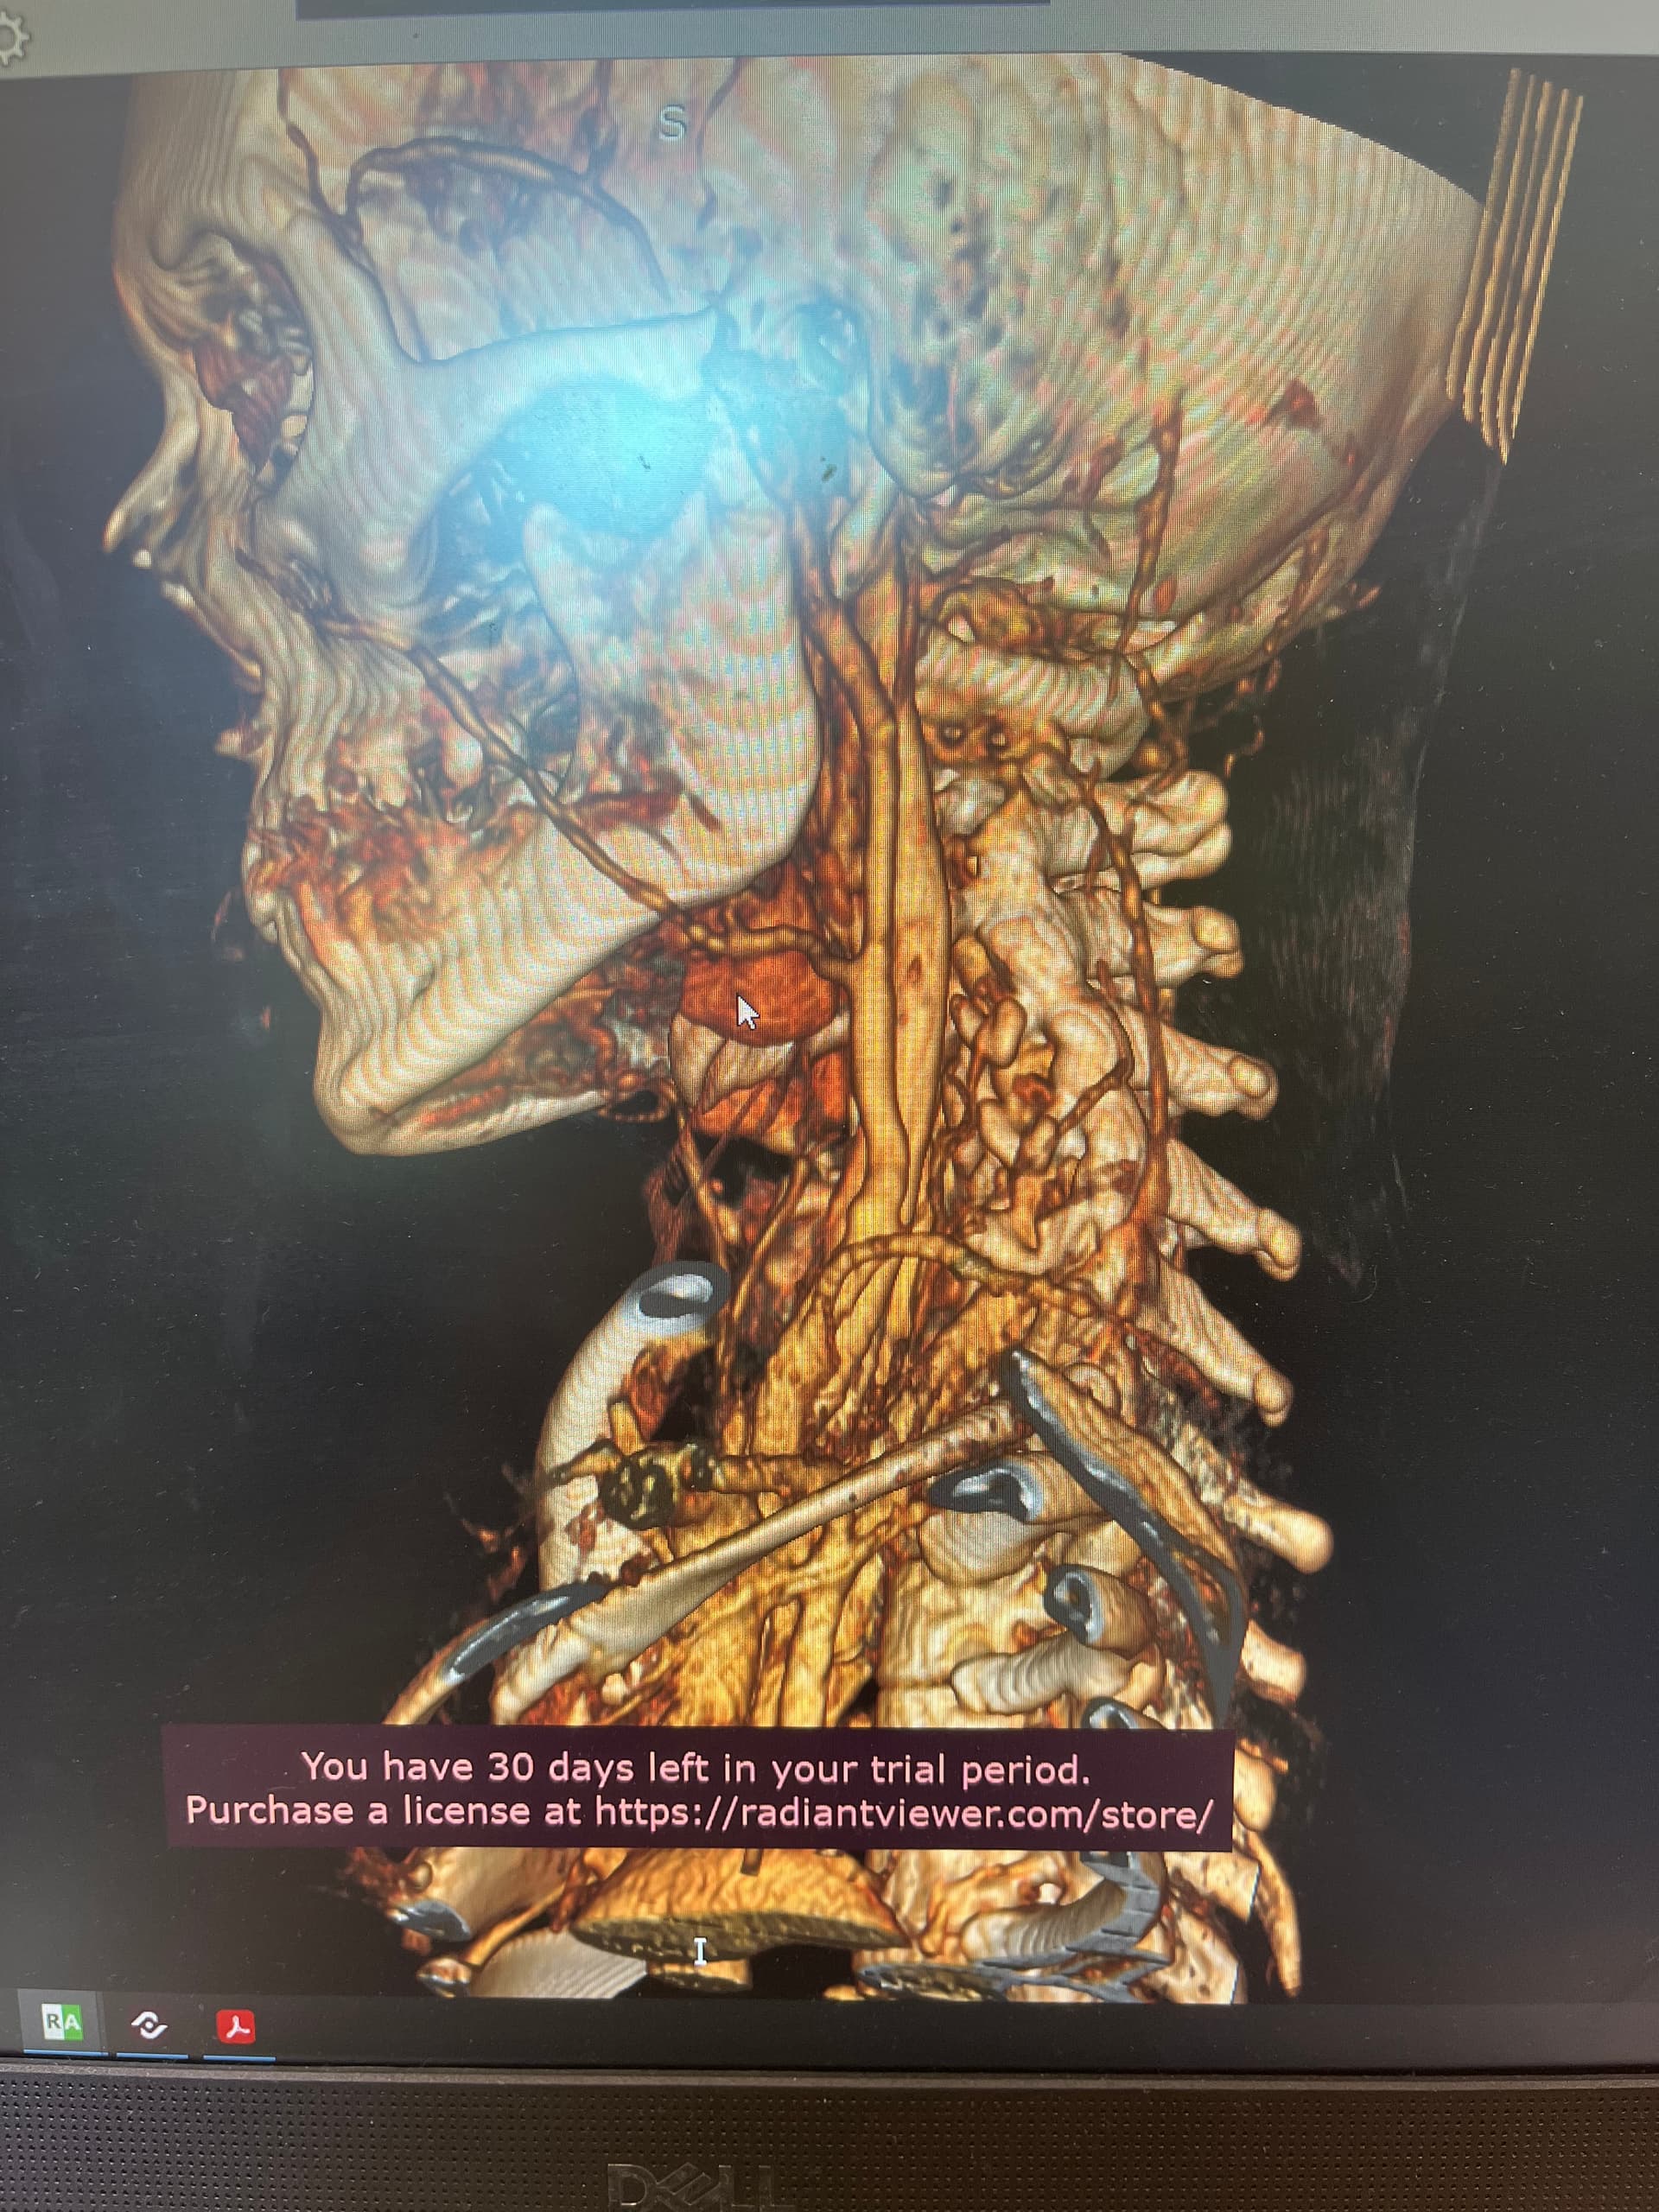

Might want to check out left styloid process and ligament also. Can see it on the 3D but not all of it due to blood vessels. Might be contributing to the hyoid injury/problem if ligament is calcified.

@leo - The new symptoms you’ve just mentioned i.e. dizziness, headaches, brain fog, weird throbbing in my neck and head are all those we see associated with internal jugular vein compression. From what I can see in the images you posted, it looks like you may have that going on, but I’ll let @TML give you more information.

Hi, good catch! I do have an elongated styloid on the left side too. And calcification on my ligaments as well, per my ct report. I’ve been wondering how much that plays into what’s going on now. I felt a lot of relief from the poking after my first styloidectomy, so I had decided to wait on my second one for awhile, then this injury happened.